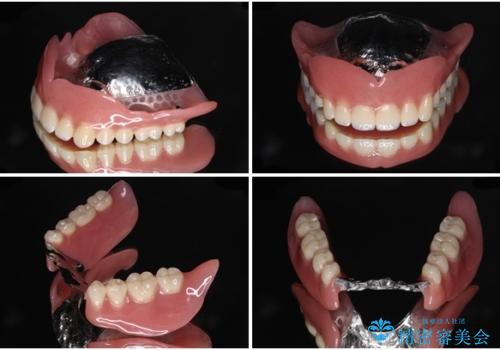

近年の入れ歯は、クラスプという金属のバネのない、ノンクラスプデンチャーが主流となってきており、金属がほとんど使用されなくなっています。しかし、両隣の歯にぶら下がる部分には金属によるフック(レスト)を用いることが、咬み合わせや周辺の歯の安定に大きく寄与するため、今回もレストのみに金属を使用したノンクラスプデンチャーを製作しました。